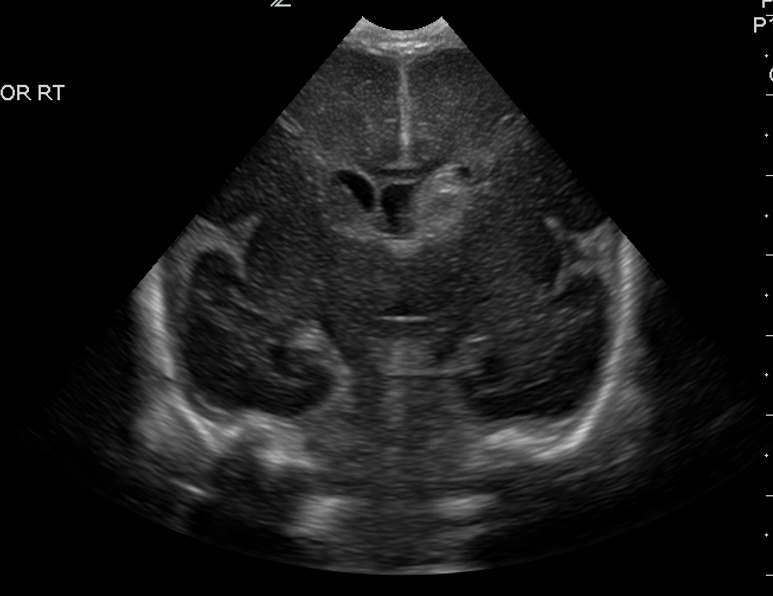

CSF spaces/ventricular system

There is a prominence of the extra axial fluid spaces. [Yes/No]

There are debris/septations in the extra axial fluid spaces. [Yes/No]

There are debris/septations in the ventricles. [Yes/No]

There is a subdural collection on the right/left side. [Yes/No]

There is prominence of the ventricular system. [Yes/No]

There is an asymmetry of the ventricular system. [Yes/No]

There is a cavum septum pellucidum. [Yes/No]

There is a midline shift towards right/left. [Yes/No]

The lateral ventricle/s are dilated. [Yes/No]

The third ventricle is dilated. [Yes/No]

The 4th ventricle is dilated. [Yes/No]